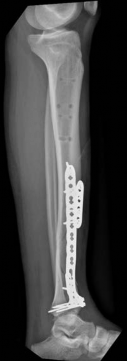

With the articular surface reconstituted, the surgeon's focus shifts to bridging the complex metaphyseal-diaphyseal dissociation. A pre-contoured anatomical locking plate is slid submuscularly or subcutaneously along the diaphysis using a MIPPO technique. The plate is positioned on the anterolateral or medial surface, depending on the preoperative plan and soft tissue constraints.

The distal portion of the plate is secured to the reconstructed articular block. It is imperative that the distal locking screws are placed parallel to the joint space, forming a rigid subchondral raft that supports the articular cartilage. Fluoroscopy is utilized extensively to ensure no screws have penetrated the joint. Once the distal block is secured to the plate, the diaphyseal segment is aligned. Length, alignment, and rotation are restored using manual traction or the femoral distractor. The proximal portion of the plate is then secured to the diaphysis using a combination of non-locking screws (to pull the bone to the plate) and locking screws (to create a fixed-angle construct). The working length of the plate is maximized by leaving several screw holes empty over the zone of comminution, promoting secondary bone healing.